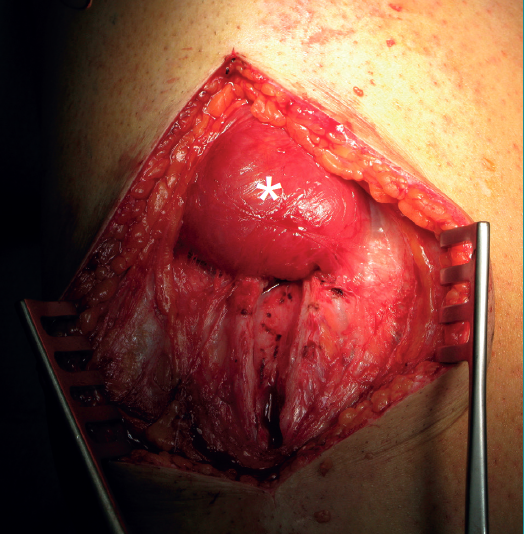

Figure 5. Right thigh. The head of the patient lies at the upper part of the image. "Degloving" lesion of the rectus femoris, with characteristic retraction of the proximal stump (asterisk).

It is also important to identify another type of injury particular to the RF, namely degloving injury, characterized by an apparent dissociation of the deep component (bipennate) from the surrounding component (unipennate). This dissociation may extend 4-18 cm and occur with or without significant retraction (Figure 5). Since these lesions appear to manifest more often at the periphery of the bipennate internal muscle belly than at the myotendinous junction, they could be defined as injuries of that muscle belly(21).